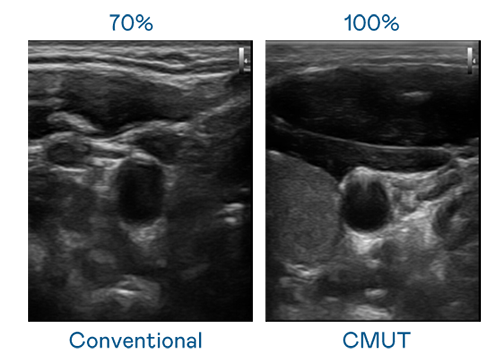

CMUT 技术是一种用电容式微机电元件来产生超音波讯号的技术。与传统 PZT 压电式技术相比,CMUT 频宽增加 30%,更宽频的超音波讯号让影像解析度大幅提升,是实现高影像品质医疗超音波扫描、促进精准医疗发展的关键技术。

大频宽带来超清晰影像

超音波影像的解析度高低,首先取决于探头能发出的讯号频宽。九游会j9 CMUT 可提供高清晰的超音波讯号,提供高频宽、高灵敏度、影像纹理细节更高的超音波影像,协助医护人员缩短影像判读时间及利用精准的医疗影像进行诊断。